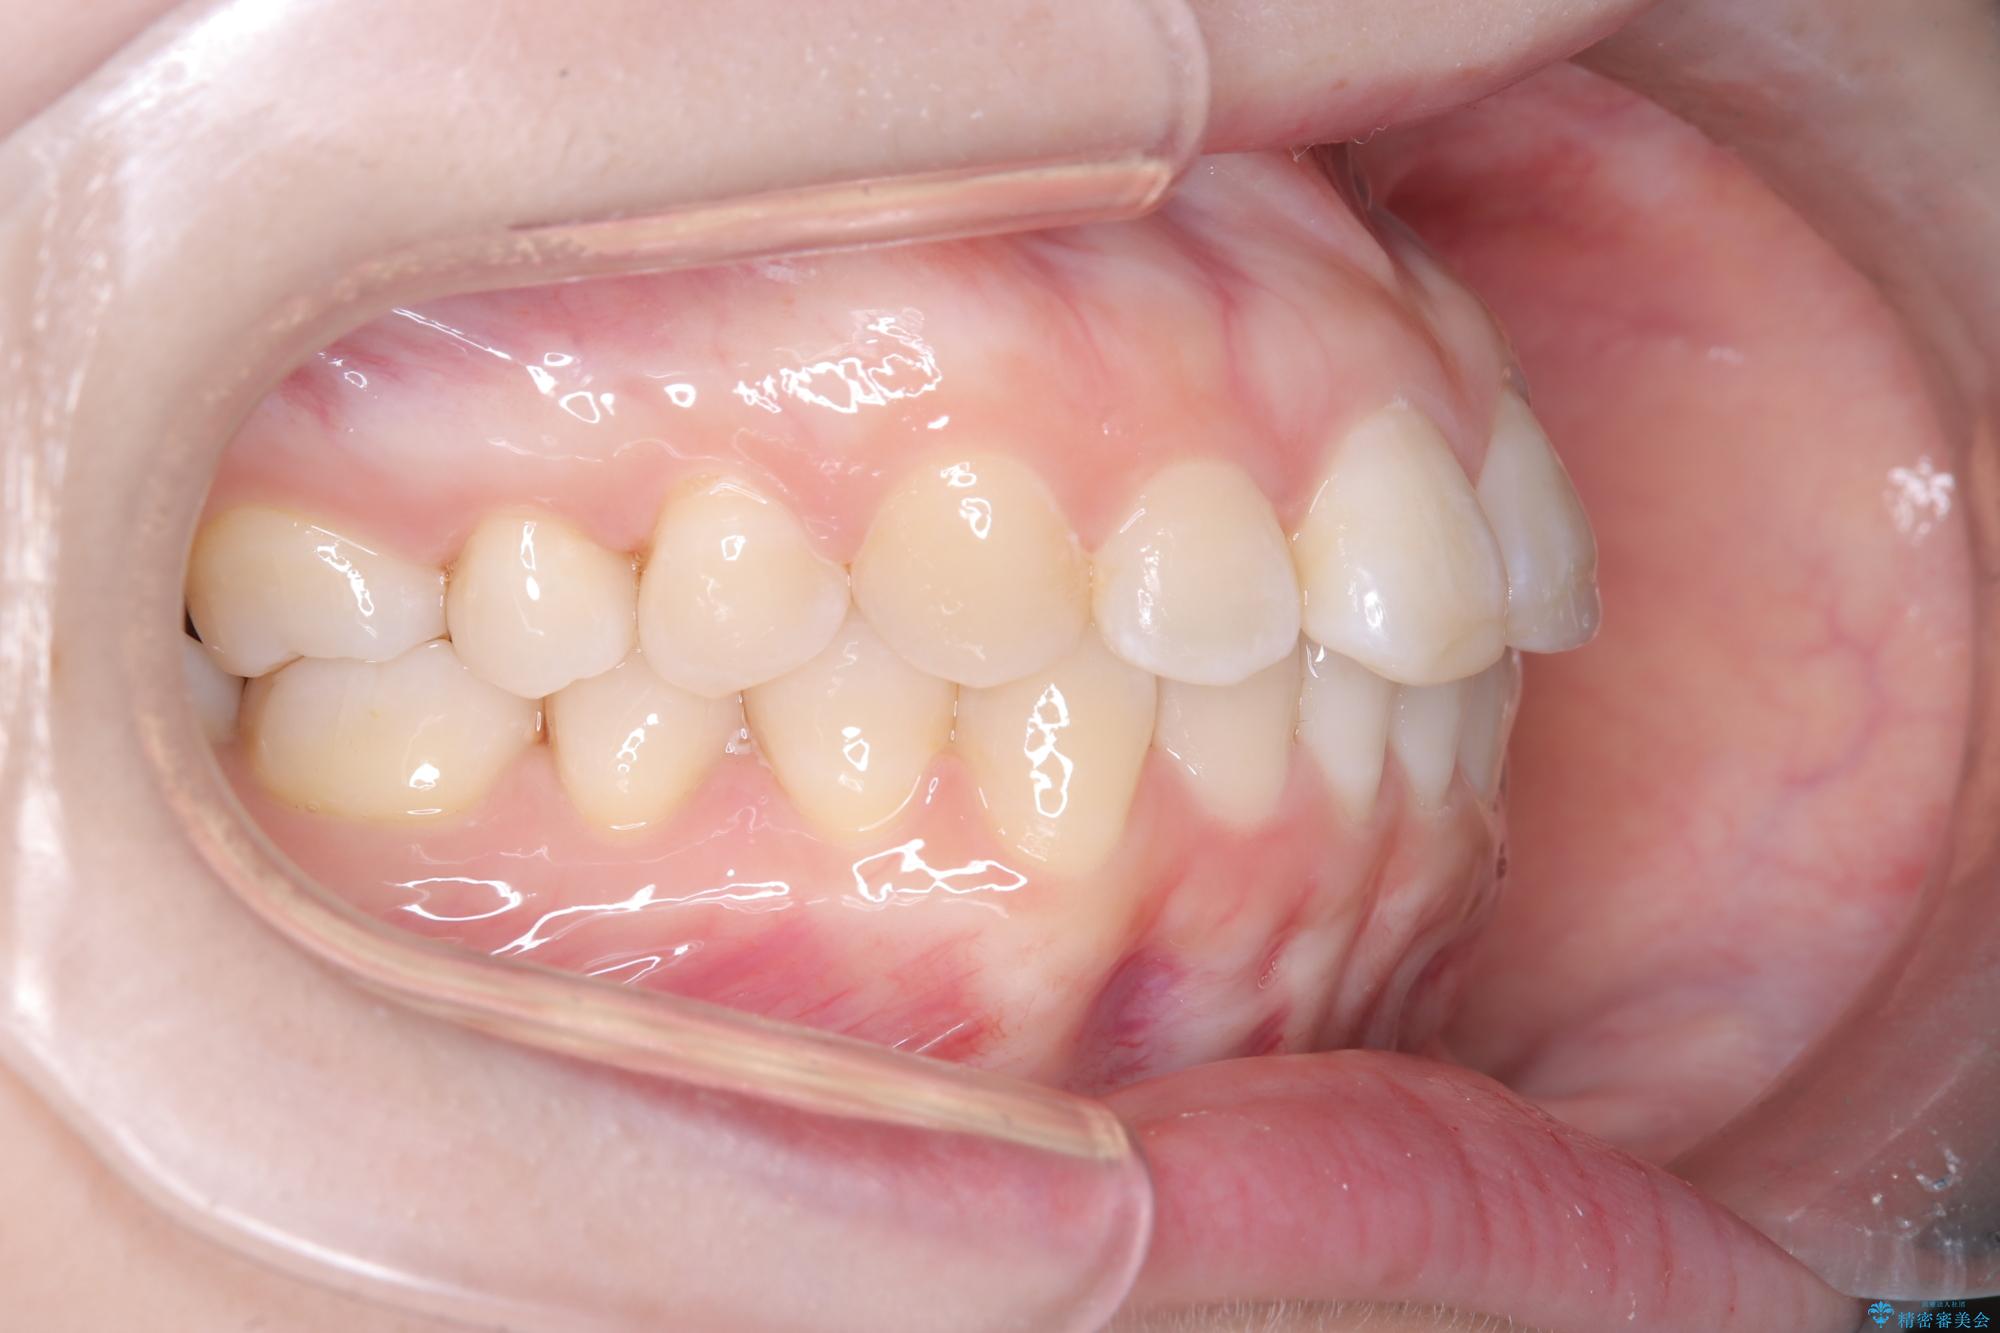

- 前歯のデコボコ(叢生)を気にされてご来院されました。精密な検査の結果、歯が並ぶスペースが不足していることが判明。患者様のご希望から、透明で目立ちにくいインビザライン(マウスピース矯正)による治療計画を立案しました。抜歯を避け、奥歯全体を奥へ動かす遠心移動という方法でスペースを確保し、前歯の叢生を解消することを目指します。

今回の矯正治療では、透明なマウスピース型の装置インビザラインを使用しました。この装置は取り外し可能で、日常生活で目立ちません。治療は、緻密に計算された計画に基づき、段階的に作製されたマウスピースを交換していくことで、奥歯から順に全体を後方へ移動させる遠心移動を実施。これにより、前歯を並べるための十分なスペースが確保され、デコボコが解消されました。抜歯することなく、機能的にも審美的にも整った美しい歯並びを獲得していただけました。